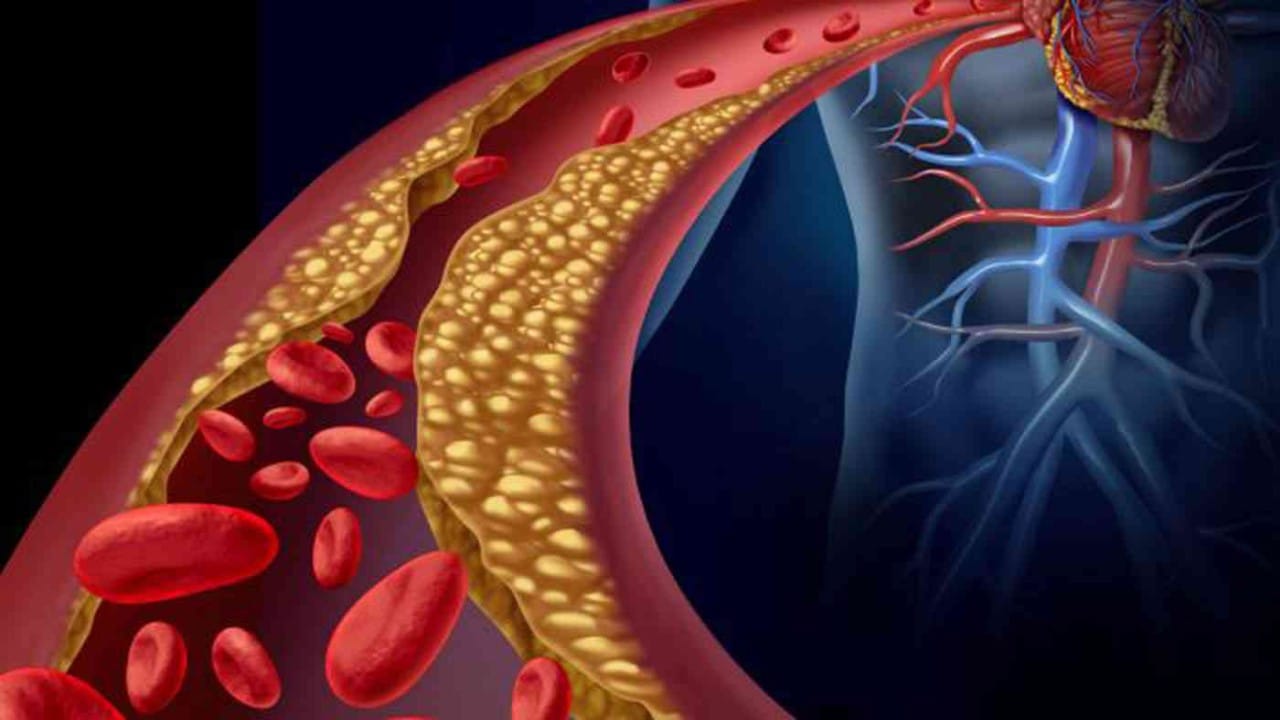

عوامل زيادة خطر الإصابة بارتفاع الكوليسترول

علامة بالقدمين تشير لزيادة الكوليسترول